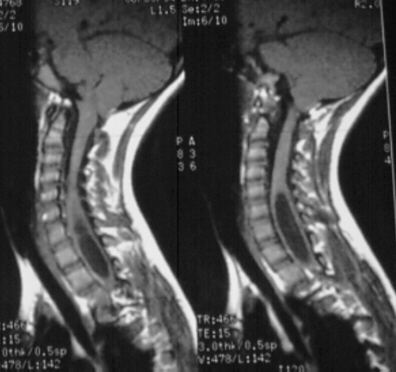

A 10 year old female presented with a spinal curvature which was first noted in a routine camp physical. She had no neurologic complaints. Her birth, medical, and developmental history were all unremarkable. Her family history was negative except there was a vague history of spinal curvature in the father. Physical examination was significant for a moderate left thoracic rib prominence, normal lower extremity reflexes, sensation and strength, but an absent abdominal reflexes in the upper and lower quadrants on the left side. A 24 degree left thoracic curve from T5 - Tl1 was measured (image 1). Also noted was an Arnold-Chiari malformation (image 2).

Decompression of this lesion is indicated because this will probably prevent the scoliosis from progressing.

The presence of syringomyelia and scoliosis should raise the concern about the possibility of an occult spinal cord tumor.

A syrinx should be suspected in a child if the spinal canal on AP x-ray at C5 is wider than the body of C6.